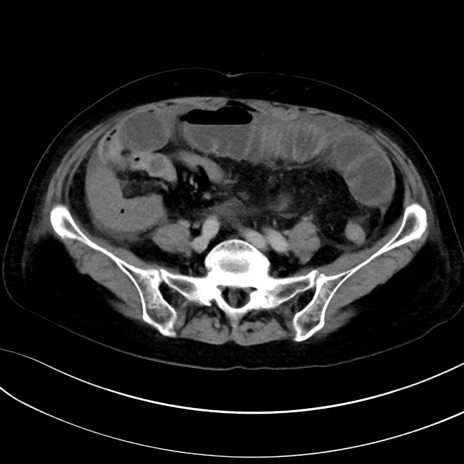

症例13 CT(横断像)1日半後